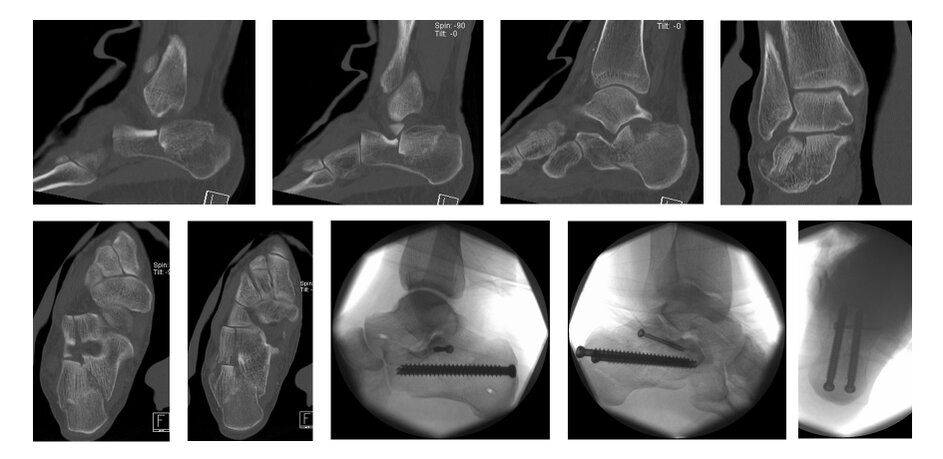

case 15FM, 34y, male, depression-type, surgery on 2nd day after trauma, chain smoker